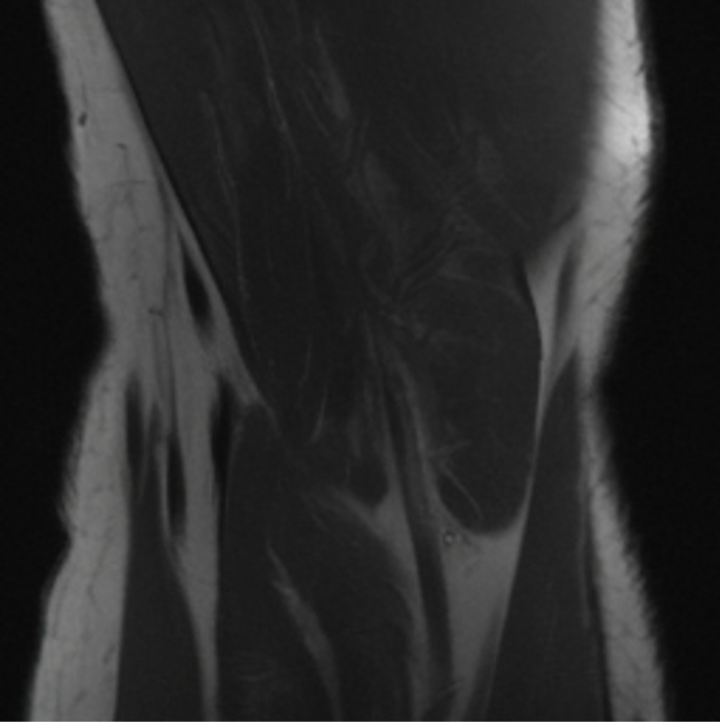

5.3 Out-of-Domain Generalisation

One way to test the generalization capability of the trained X-Diffusion is to test it on a completely different domain from an MRI dataset not seen during training. We report the single-slice results on NYU fastMRI [37, 82], a knee MRI dataset, using the X-Diffusion trained on the BRATS brain MRIs. The results are shown in Figure 9 and Table 2. It shows how successfully X-Diffusion is able to generate knee MRIs from a single image, despite not seeing knees at all in training. To qualitatively assess how realistic our generated 3D volumes were (produced from a single slice), we gave 20 generated examples alongside their real MRI counterparts to an expert orthopaedic surgeon. He was then asked to identify the real example from a given pair. The surgeon identified with certainty only 10 real knee MRIs out of 17, while could not decide on the remaining 3 of the 20 MRI pairs. This further validates the generated out-of-domain MRIs.